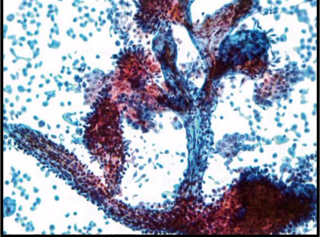

LGUN features

papillary groups w/fibrovascular core

transitional cell papilloma features

BENIGN, papillary groups w/scant fibrovascular core